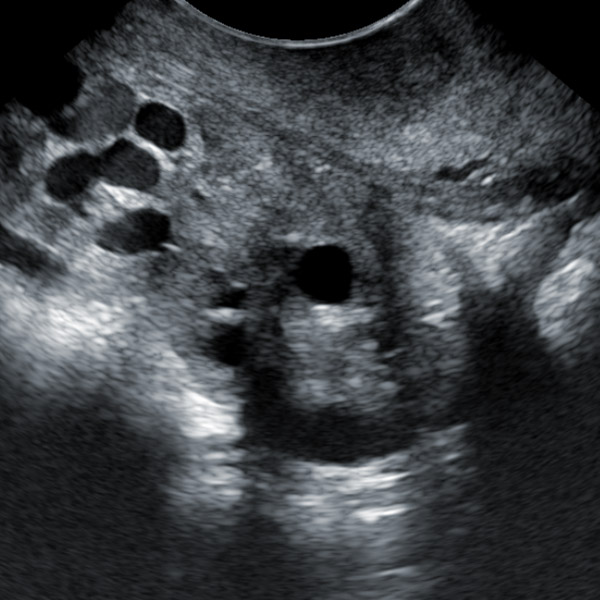

6. High-frequency probe and high-quality Doppler color ultrasound images can observe the situation of follicles below 1mm.

IV. Features of animal backfat eye muscle probe:

1. 18cm long professionally designed backfat eye muscle probe, which can fully test the backfat eye muscles of various animals

2. The probe scanning depth can reach 30cm, which can well present the eye muscles of large animals

3. High-frequency probe and high-quality Doppler color ultrasound images can well identify the measured muscle quality grade